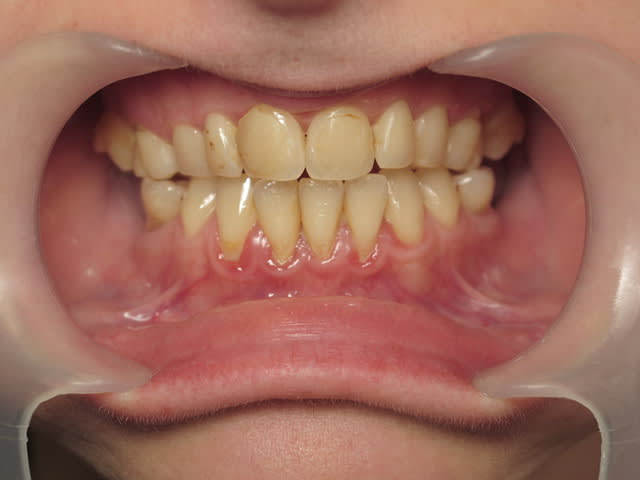

Patiente de 33 ans, questionnaire de santé RAS, demande esthétique. Elle souhaiterait que ses dents soient "davantage visibles" lors du sourire. Les dents absentes sont dues à des agénésies.

facettes maxillaires 13 à 23,implants postérieurs mandibulaires après une étude de l'occlusion sur articulateur (améloplasties des cuspides dv de 16 et 26?); valider le montage facette éventuellement avec un mock up (si la patiente consulte uniquement pour une question esthétique, autant ne pas se planter). voilà pour moi

Ajoute un peu de paro, des greffes , des facettes de 6 a 6 ( 3 a 3 pas suffisant).

Pour moi paro, puis orthodontiste, puis implants et enfin esthétique avec facettes 6 à 6.

+1, et malheureusement il y a fort à parier que l'ODF a été fait. C'est dans l'idéal un cas ortho-chir, puis eclairssissement et un peu de maquillage pour l'esthétique (certainement facette à tous les étages si on veut être élitiste, mais déjà avec la chir. on devrait rendre ce sourire largement plus agréable). Pour 33 ans la patiente semble très marquée, ce doit être lié au manque de croissance du maxillaire ( le profil est il concave?), associé à un menton légèrement allongé. Un joli petit cas pour un maxillo.

Perso, ça me fait un peu halluciner que tu ne te rendes pas compte que des facettes vont juste lui prendre du pognon, pas lui redonner la visibilité de ses incisives, sauf à lui faire des ratiches de 2cm, et ce sera fragile et horrible. Ce qui lui manque (on a confirmé que le profil est concave) c'est une croissance antérieure et je pense vers le bas du maxillaire, elles sont très bien (quoiqu'un peu jaunes sur la photo), ses incisives!